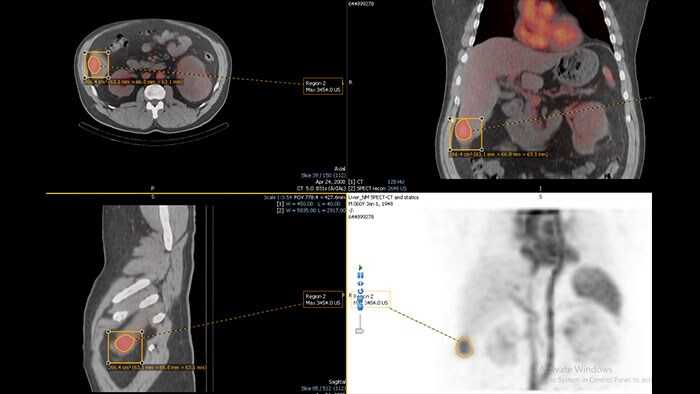

Streamlined workflow for follow up and analysis of oncology patients

MMTT is a post processing software used to display, process, analyze and quantify anatomical and functional images, for CT, MR, PET/CT, SPECT/CT and Dual Energy CT at one or multiple time points.

Enhanced user experience for NM reading with a leading NM viewing solution

A comprehensive NM solution, designed to enhance productivity of PET/CT and NM reading. It offers a solution for handling multiple studies requiring rigorous quantification of MV data**.